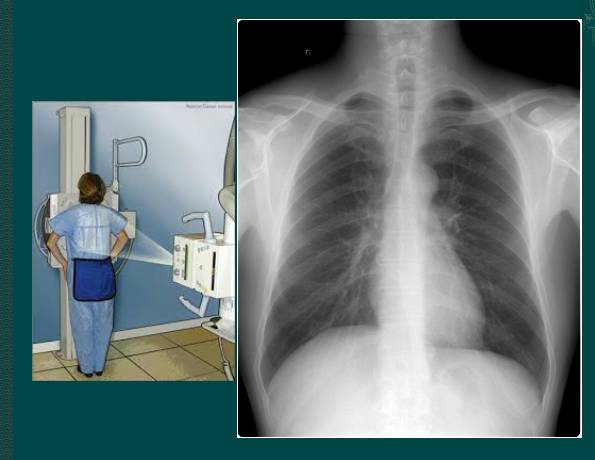

1. 胸部正位片

临床拍标准的胸部正位片其实是后前位片,如上图。

上图为正常胸部后前位片